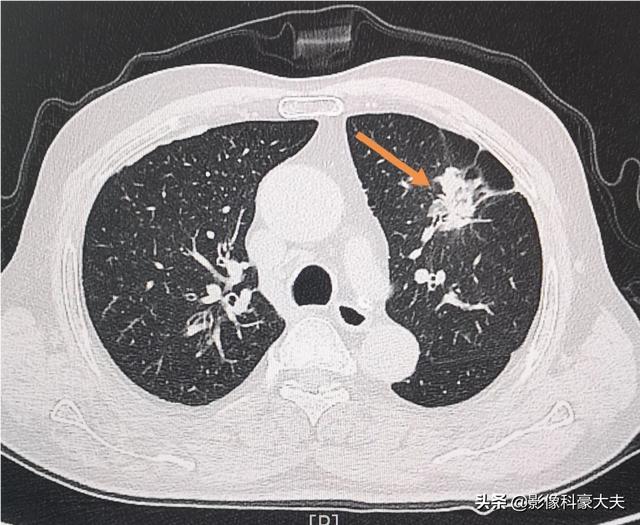

今日お会いした前立腺肥大で排尿困難の患者さんで、手術に備えてのことです。手術前のルーチンは、何か大きな病気を除外するための精密検査が必要で、その結果、左側の肺に腺がんが見つかりましたが、まだ肺の症状は出ていません。

この時点では、まず前立腺の手術は無理で、肺がんを緊急に取り除かなければならない!